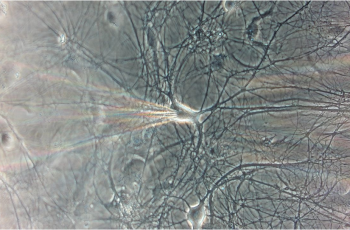

Primary E18 rat cortical neurons were enzymatically and mechanically dissociated and plated at low density on a monolayer of cortical astrocytes. Neuronal cultures were maintained with regular medium changes and recorded between 14–21 days in vitro, a timeframe selected to support stable synaptic receptor expression. Whole-cell voltage clamp electrophysiology was performed using standard instrumentation and acquisition software.